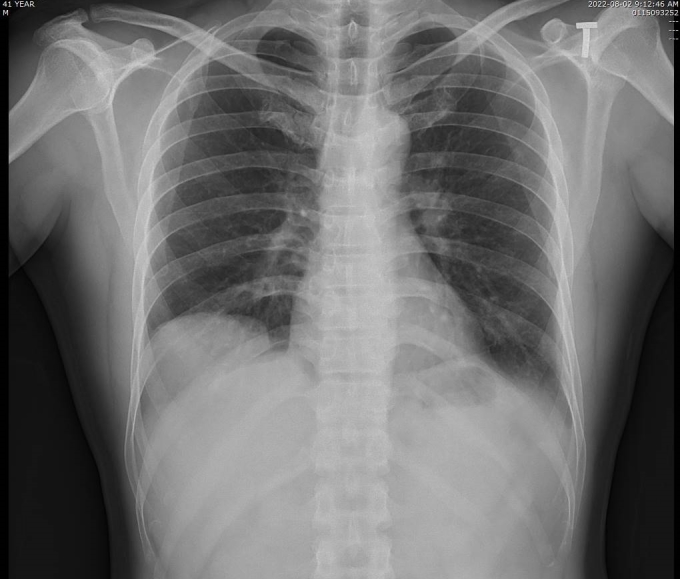

Hình ảnh X-quang phổi của bệnh nhân bị nhão cơ hoành khiến tạng dưới ổ bụng di chuyển lên trên gây xẹp thùy dưới phổi phải. Ảnh: Bệnh viện cung cấp

Kết quả chụp cắt lớp vi tính tại Bệnh viện đa khoa tỉnh Quảng Ninh cho thấy vòm hoành phải của bệnh nhân cao, gan di chuyển lên trên gây xẹp thụ động nhu mô phổi lân cận. Bác sĩ chẩn đoán bệnh nhân bị nhão cơ hoành phải, chỉ định phẫu thuật nội soi tạo hình cơ hoành.

Bác sĩ cho biết nhão cơ hoành là bệnh lý hiếm gặp, khó phát hiện và dễ bị chẩn đoán nhầm với các bệnh khác, như nang thùy dưới phổi, viêm phổi, bệnh phổi biệt lập... do các triệu chứng không đặc trưng, thường phát hiện tình cờ khi chụp X-quang phổi.